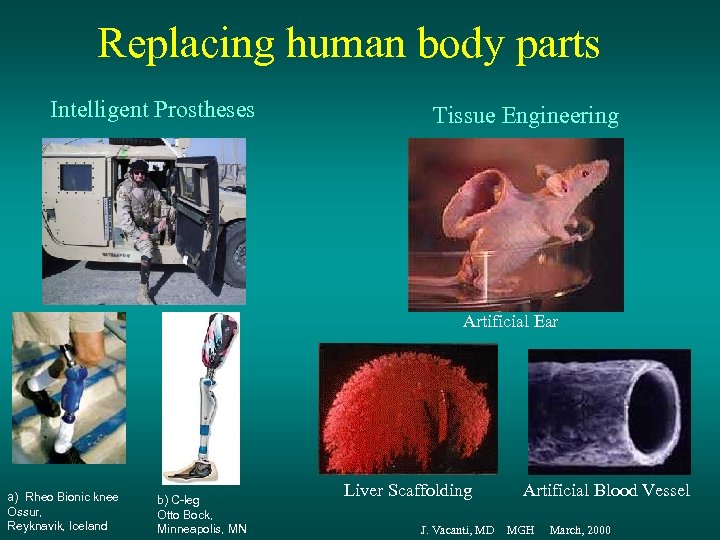

Replacing human body parts Intelligent Prostheses Tissue Engineering Artificial Ear a) Rheo Bionic knee Ossur, Reyknavik, Iceland b) C-leg Otto Bock, Minneapolis, MN Liver Scaffolding Artificial Blood Vessel J. Vacanti, MD MGH March, 2000

Replacing human body parts Intelligent Prostheses Tissue Engineering Artificial Ear a) Rheo Bionic knee Ossur, Reyknavik, Iceland b) C-leg Otto Bock, Minneapolis, MN Liver Scaffolding Artificial Blood Vessel J. Vacanti, MD MGH March, 2000